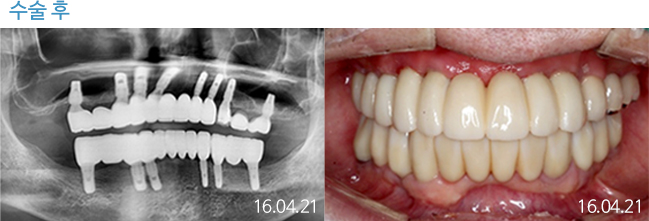

한 번 잘 심으면 10년 뒤에도 끄떡없는

더와이즈 임플란트

첨단 장비를 이용한 정확한 진단, 안정성이 입증된 정품 재료 사용,

노하우가 풍부한 숙련된 의료진의 시술 등이 임플란트 수명을 결정합니다.

※ 실제 본원에서 치료 받은 환자의 동의를 얻어 게재했습니다.

개인의 특성에 따라 부작용이 발생할 수 있으므로 담당의와 충분히 상의하시길 바랍니다.

THEWISE 치료별 전후사진